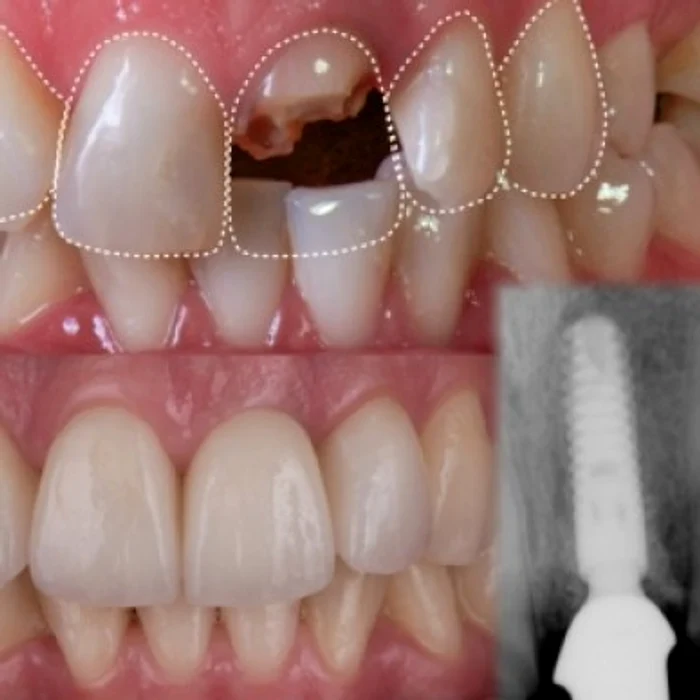

1. Ce este un implant dentar? Implantul dentar este cea mai avansată terapie pentru înlocuirea unui dinte lipsă. Implantul în sine este o rădăcină artificială din titan care se inseră în os. Pe el se va fixa un bont protetic, care va susţine viitorea coroană sau lucrare dentară.

Previne resorbţia osoasă, împiedică migrarea dinţilor antagonişti, se păstreză intacţi dinţii vecini, oferă posibilitatea efectuării unor lucrări fixe cimentate sau înşurubate acolo unde technicile clasice indică lucrări mobile sau mobilizabile.

Ambele sunt soluţii fezabile pentru a înlocui dinţi lipsă. Per ansablu, implanturile câştigă mai multă popularitate, pentru că au mai multe avantaje, după cum sunt enumerate mai sus. În plus, confortul pacientului este mai mare, potenţialul estetic este mai mare. Implanturile dentare sunt prima opţiune în cazul dinţilor lipsă, dar nu sunt o indicaţie absolută, uneori o punte dentară poate avea mai multe indicaţii. Fiecare caz trebuie tratat individual, cântărind cu atenţie raportul costuri-beneficii, respectiv riscuri la fiecare opţiune medicală.